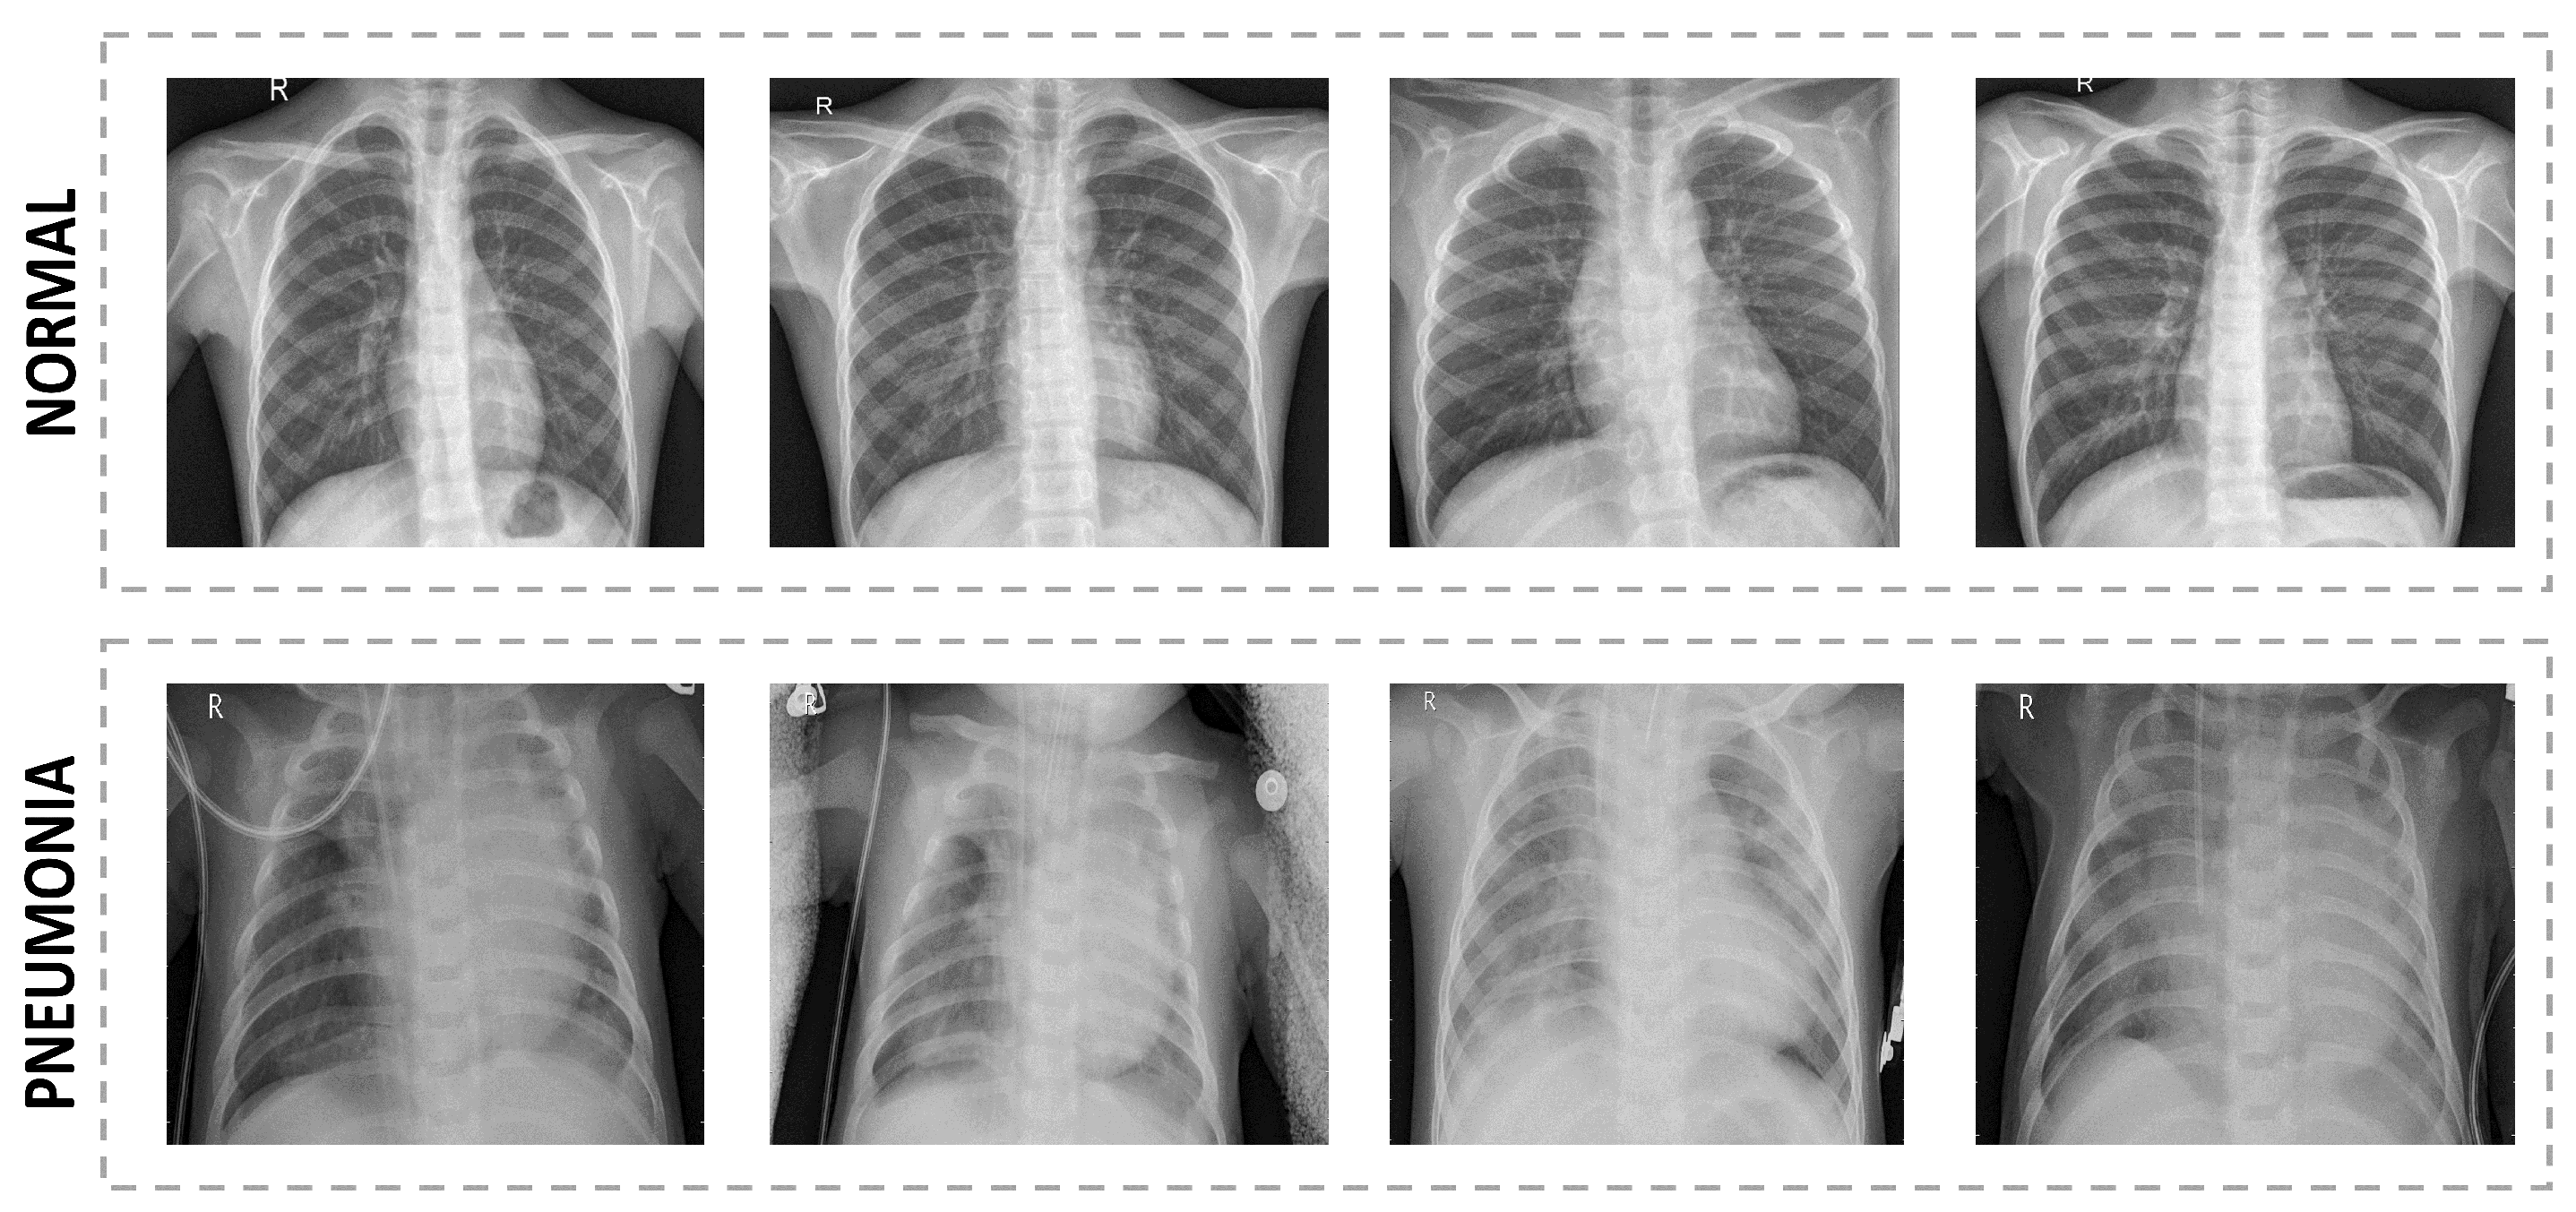

4.1. Data Set Description